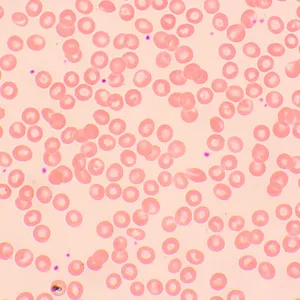

С помощью микроскопа MAGUS Bio 250TL изучают тонкие срезы и мазки биологических образцов. Исследования ведутся в светлом поле в проходящем свете. В качестве осветителя выступает 3-ваттный светодиод, а оптика включает планахроматические объективы, рассчитанные на бесконечность. Микроскоп поддерживает установку дополнительных аксессуаров, в том числе устройств для работы по методам темного поля, поляризованного света и фазового контраста. Этот микроскоп – идеальный выбор для лабораторной диагностики, научных исследований и обучения.